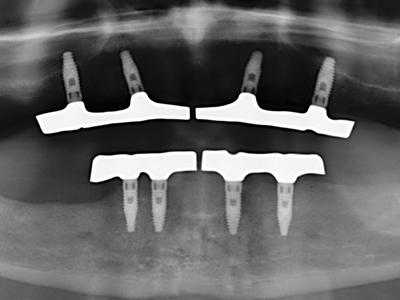

Fig. 14: Incorporación de cuatro implantes RSX cónicos (Bego Implant Systems, Bremen).

Fig. 15: El control radiológico realizado al cabo de un año muestra una estabilidad del nivel óseo.

Fig. 16: También condiciones intraorales estables con incorporación de los implantes en la encía queratinizada.